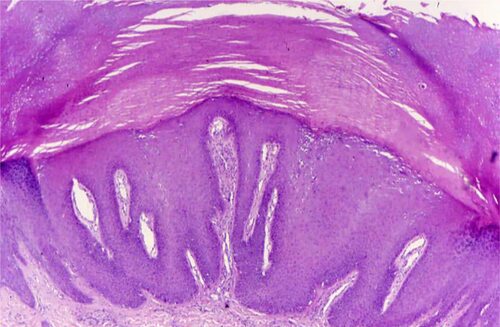

Красный плоский лишай в полости рта - это редкое заболевание, характеризующееся появлением красных плоских пятен на слизистой оболочке рта. Это состояние может быть болезненным и вызывать дискомфорт при приеме пищи и говорении.

Симптомы красного плоского лишая в полости рта могут включать:

- Красные плоские пятна на слизистой оболочке рта

- Болезненность и жжение в области поражения

- Трудности при приеме пищи и говорении